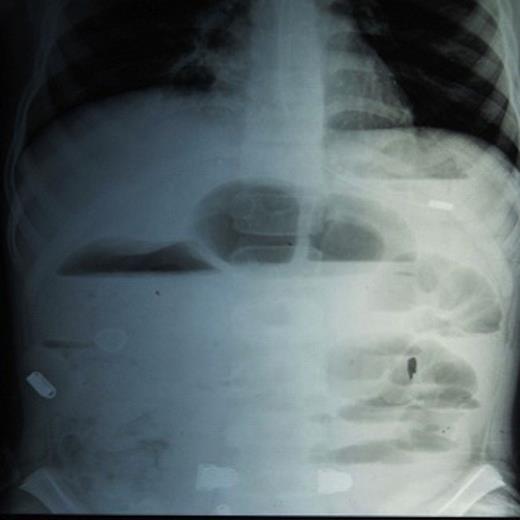

A 15 year old male child, presented with complaint of cholicky abdominal pain since 7 days and distension since 3 days. He had a past history of pulmonary tuberculosis and was a defaulter. On examination, the abdomen was mildly distended and tenderness was present in the periumblical region. A firm to hard mobile mass approximately 5 cm. x 7 cm. in size was palpable in umbilical region. It was intra-abdominal and intra-peritoneal. Bowel sounds were exaggerated. Per rectal examination was normal. ESR was 110 mm in 1st hr. On plain X-ray examination, significant air fluid levels and dilated small bowel loops were found (Fig.1).

X-ray film showing significant air fluid levels and dilated small bowel loops.